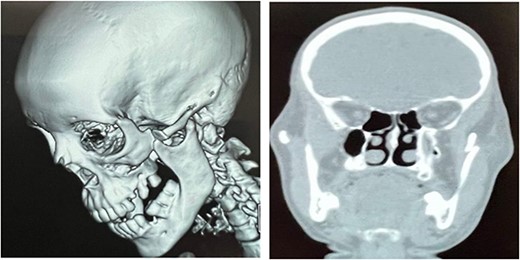

Postop Computed tomography (CT) scan demonstrated a reduced zygomatic bone with no impingement or dislocation of the coronoid process and reduction of the condyle subluxation (Fig. 6).